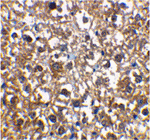

Immunohistochemical staining of rat liver cells using IRAK-M antibody at 2 ug/mL.